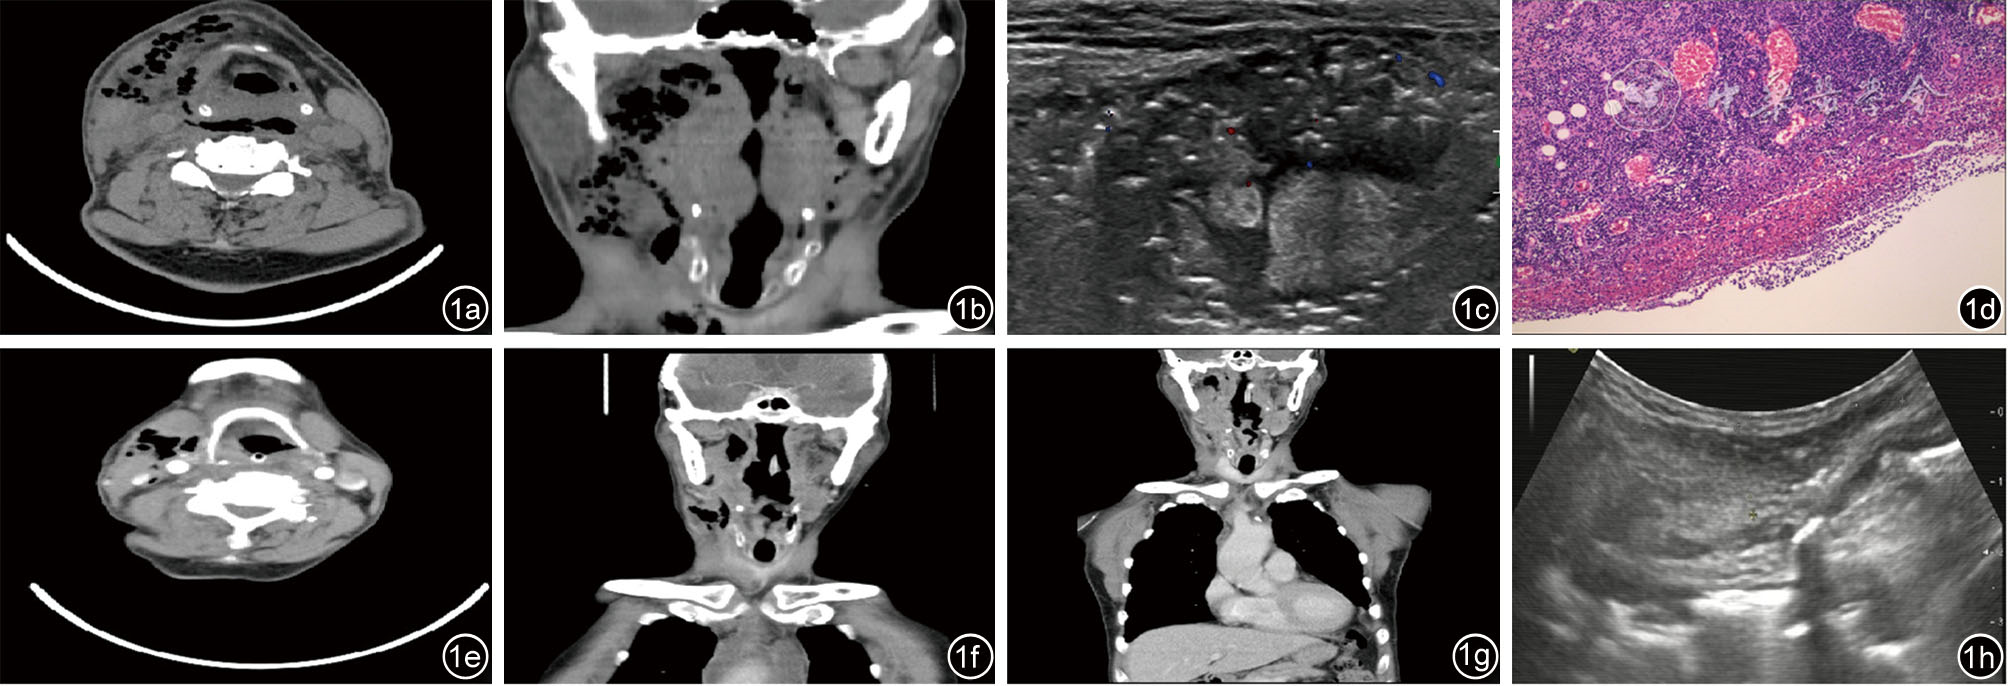

图1 病例一患者影像病理学资料。图1a~1b为颈深间隙感染患者术前颈部CT;图1c为术前颌下腺浅表肿物彩超;图1d术中快速石蜡病理切片;图1e~1f为术后1周颈部CT;图1g为术后3周颈部CT;图1h为术后颌下腺浅表彩超

1 男性 69 右扁桃体周围、右咽旁咽后、右颌下间隙、右颈深部、纵隔脓肿,肺病感染,菌血症,肺气肿 右侧腭扁桃体、颌下区低密度灶伴积气,前纵隔内积气。 经口右侧扁桃体等离子切除+内镜辅助右扁桃体周围脓肿及右咽旁咽后、右颌下、右颈深脓肿切开引流术 (右侧扁桃体)黏膜急慢性炎 好转